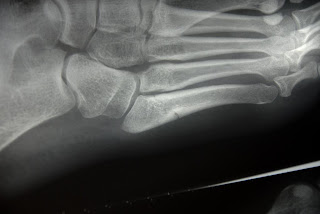

I broke my foot.

Now, this might seem like a disaster to most people. But after pursuing the x-rays, and having some deep thoughts about my pain tolerance, I decided that the only thing for it is to walk it off. I'm moving to Norway in a week, which for a number of reasons would be extremely difficult to postpone.

At first I thought it was no big deal - I had minor stress fractures in both feet last year, and they hurt sometimes. So I assumed I just tweaked it again. But after some intense pain and realizing I couldn't walk, we had to ask some fellows to call me an ambulence and I spent the night in a Scottish hospital. Hellooo Scotland.

I was scared they would give me a cast, which would mean my trip is over (I can't handle a plaster cast in snow). But the wonderful doctor said he could give me a removable walking cast, and he expects it to be better in about 6 weeks. Since its a clean break, I can pretty much do whatever I want as soon as I feel ready. (Probably not the wisest thing to tell me, since now I'm going to walk on it ASAP).